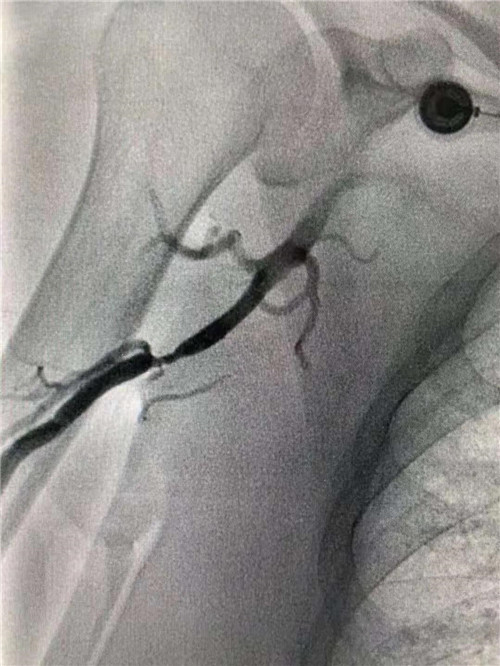

右側(cè)肱動(dòng)脈重度狹窄

快速完成右側(cè)橈動(dòng)脈穿刺,上造影導(dǎo)管受阻后,行肱動(dòng)脈造影,發(fā)現(xiàn)右側(cè)肱動(dòng)脈重度狹窄。